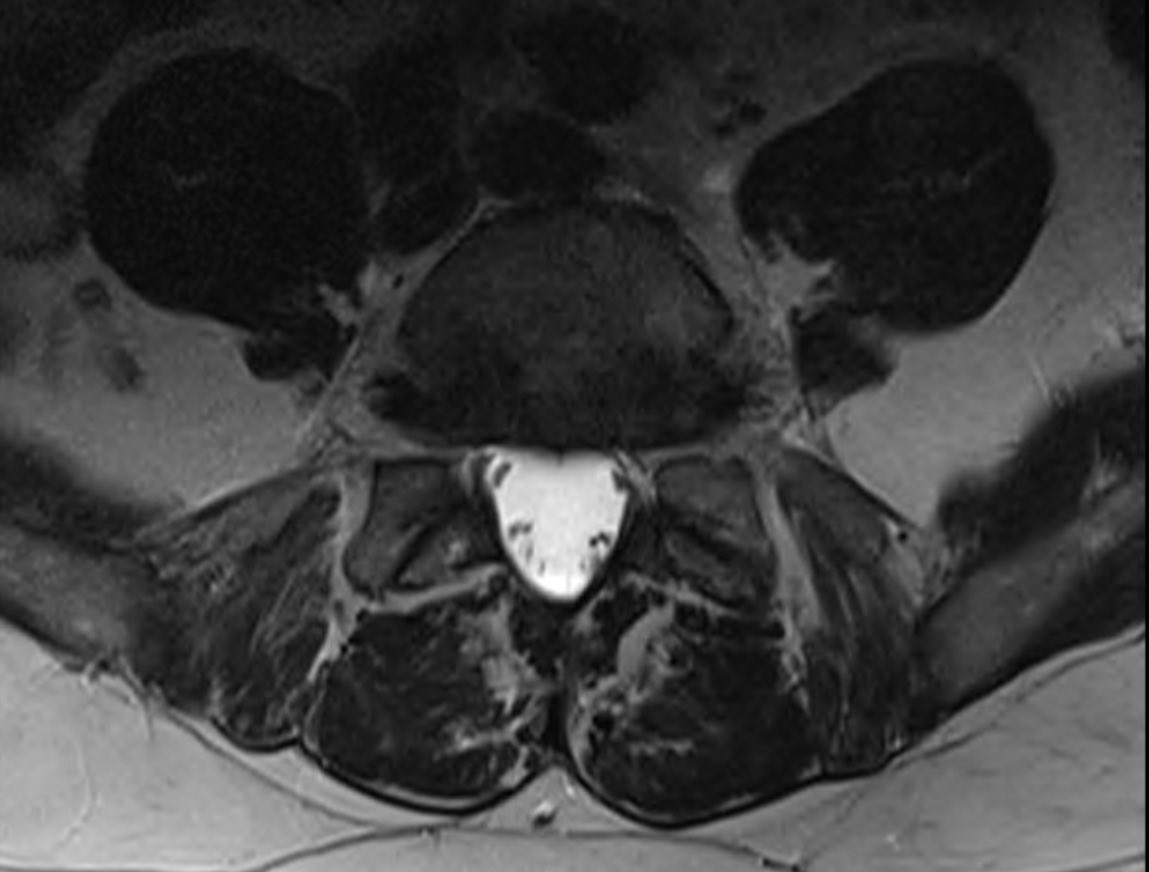

4. mri symphysis oblique axial views (& sagittal) normal - no pubic stress, conjoint tendon, add origin pathology etc